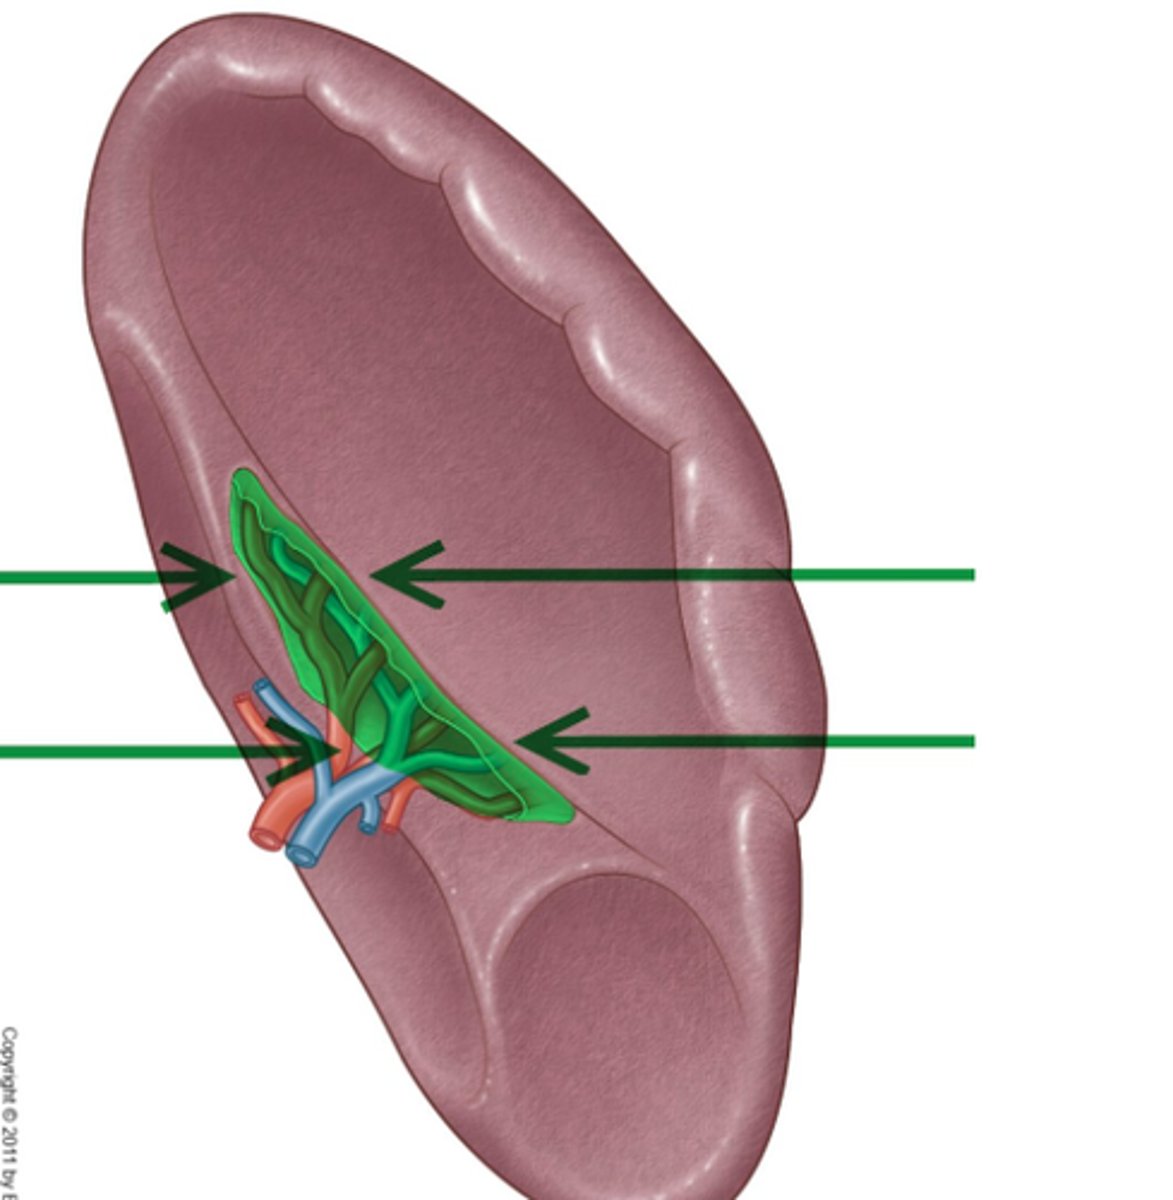

splenic hilum

site located in the middle of the spleen where blood vessels, lymphatic vessels, and nerves enter or exit the organ.

red pulp (spleen)

-is the dark red tissue in the spleen containing sinusoidal capillaries, connective tissue fibers, and immune cells like macrophages, plasma cells, and lymphocytes.

-It destroys old red blood cells, removes pathogens and toxins

-facilitates lymphocyte movement between splenic tissue and blood.

white pulp (spleen)

has whitish appearance in a fresh spleen. Lymphocytes, macrophages surrounding small branches of splenic artery